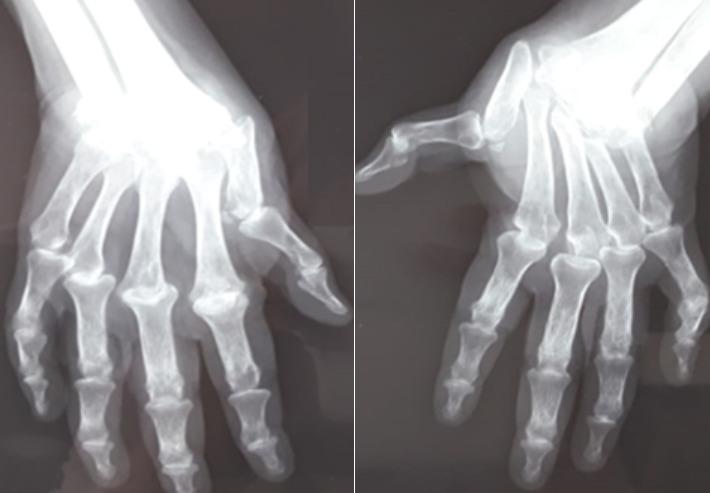

Rheumatoid arthritis rarely involves the cricoarytenoid joint, symptoms of varying severity ranging from foreign body sensation, fullness or tension in the throat, hoarseness, odynophagia, speech or cough pain to stridor and respiratory distress during bilateral paralysis of the vocal cords. We are reporting a case of rheumatoid arthritis with bilateral involvement of the vocal cords. The diagnosis was clinically made and confirmed by endolaryngoscopy, responding to antirheumatic treatment but coming to the stage of permanent tracheotomy.

类风湿关节炎很少累及环杓关节,症状严重程度不一,从咽部异物感、饱胀感或紧迫感、声音嘶哑、吞咽痛、说话或咳嗽时疼痛到双侧声带麻痹时的喘鸣和呼吸窘迫。我们报告一例类风湿关节炎累及双侧声带的病例。临床诊断并经喉镜检查证实,对抗风湿治疗有反应,但发展到需永久性气管切开的阶段。